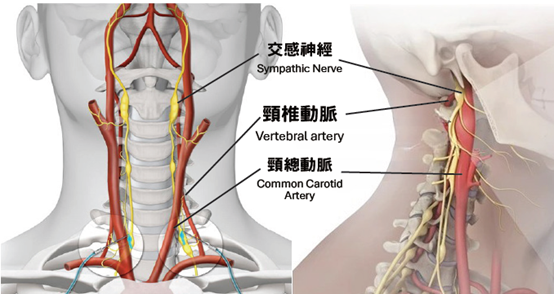

「頸源性頭暈」便是指疾病是與頸部問題最為相關。頸是連接頭部與軀幹的橋樑,它包含脊椎、血管 和神經組織(Fig.1),對活動和生存至關重要,任何傷害這條橋樑或這條橋樑出現病患,對維持人體健康或身體機能有關鍵影響,例如: 出現長期的頭暈頭痛。

(2)刺激交感神經:

抬頭或擺動頭部或頸椎,轉移體位刺激到交感神經,使頭暈、頭痛、眼花、心跳等症狀更加明顯。

(3)頸椎內外血管扭曲:

抬頭、擺動頭頸部或長期姿勢不良等,導致頸椎內外血管流動不暢順,影響血液來往腦區域,導致頭暈、頭痛。